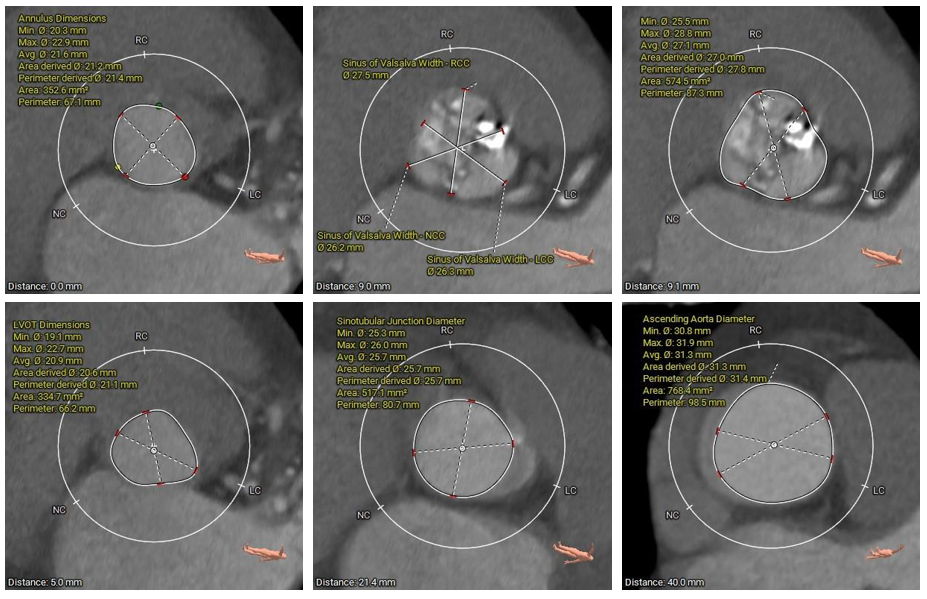

术前CT评估

• Type1型二叶式主动脉瓣,瓣叶增厚伴中重度钙化,左右窦间可见钙化融合嵴;LVOT呈类直筒型;

• 左冠脉开口高度较低,右冠脉开口高度尚可,切线位左冠瓣叶长度>冠脉开口到瓣叶附着缘距离;左冠脉可见少量钙化;

• 瓦氏窦、窦管交界内径偏小、升主动脉内径可;左室腔内径偏小,心室壁明显增厚;

• 瓣环平面与水平夹角为48°,主动脉弓弓距及夹角尚可;

•主动脉弓、腹主动脉下段、双侧髂总动脉可见散在钙化斑块;所见入路血管直径尚可。

主动脉根部测量

瓣上结构测量